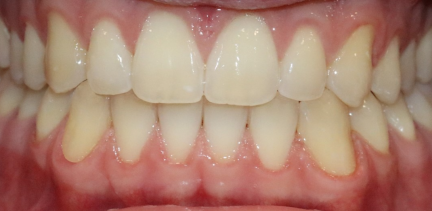

Résultats obtenus

- Relation de classe I obtenue

- -Relation de classe I maintenue

- Guidage fonctionnel des canines des deux côtés

- Articulé antérieur corrigé

- Articulé postérieur corrigé

- Surplomb et recouvrement normaux obtenus

- Surplomb amélioré

- Amélioration significative de la supraclusion

- Amélioration significative du surplomb

- Lignes médianes coïncidentes

- Bonne inclinaison axiale des incisives

- Courbe de Spee nivelée

- Arches alignées et coordonnées

- Alignement des deux arcades par dérotation

- Forme de l'arcade améliorée

- La ligne de sourire esthétique a été obtenue

- Cas où tous les objectifs du traitement ont été atteints

- Des arcades harmoniques ont été obtenues

État final